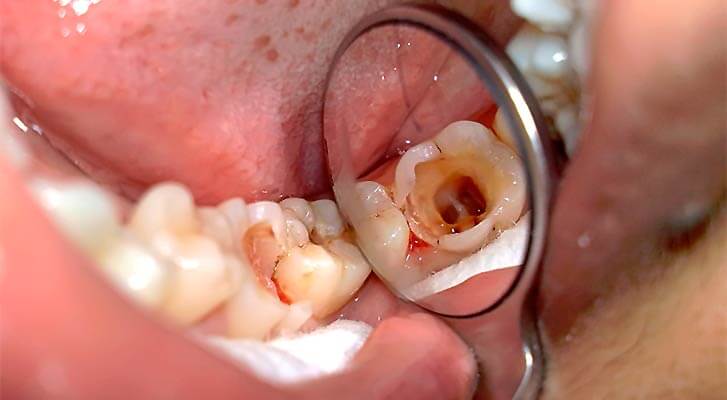

Пульпит – это воспаление сосудисто-нервного пучка (пульпы) зуба. Как правило, пульпит является осложнением кариеса и развивается в результате инфицирования мягких тканей.

Воспалительный процесс при пульпите в большинстве случаев развивается вследствие занесения инфекции в пульпарную камеру. Бактерии могут попадать в нее двумя путями – интердентально (через коронковую часть при осложненном течении глубокого кариеса) и ретроградно (из окружающих корень тканей через апикальное отверстие). В редких случаях патогенная микрофлора заносится через дентинные канальцы.

Острая форма развивается при проникновении инфекционных агентов в пульпу при закрытой камере (сквозь ее стенку, истонченную кариозным процессом). На начальном этапе воспаление серозное, очагового характера. Если лечение не проведено, практически неизбежно стремительное прогрессирование патологического процесса с появлением гнойного отделяемого. При отсутствии оттока оно давит на пульпу, что и вызывает появление интенсивных болей.